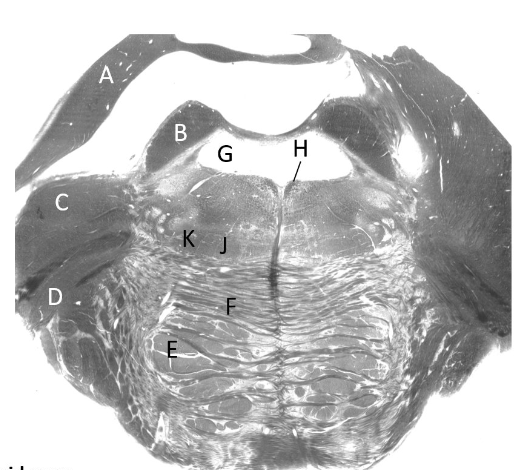

at what level is this?

spino-medullary junction

what is a?

spinal trigeminal nucleus

what is b?

nucleus cuneatus (sm)

what is c?

fasciculus gracilis (sm)

what is e?

pyramidal decussation

what is f?

spinocerebellar & (more medial) spinothalamic tract